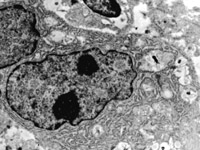

5-2-2 傷后第1天,毛細(xì)血管內(nèi)皮細(xì)胞核固縮,管腔內(nèi)血液凝集和瘀滯  TEM×6000